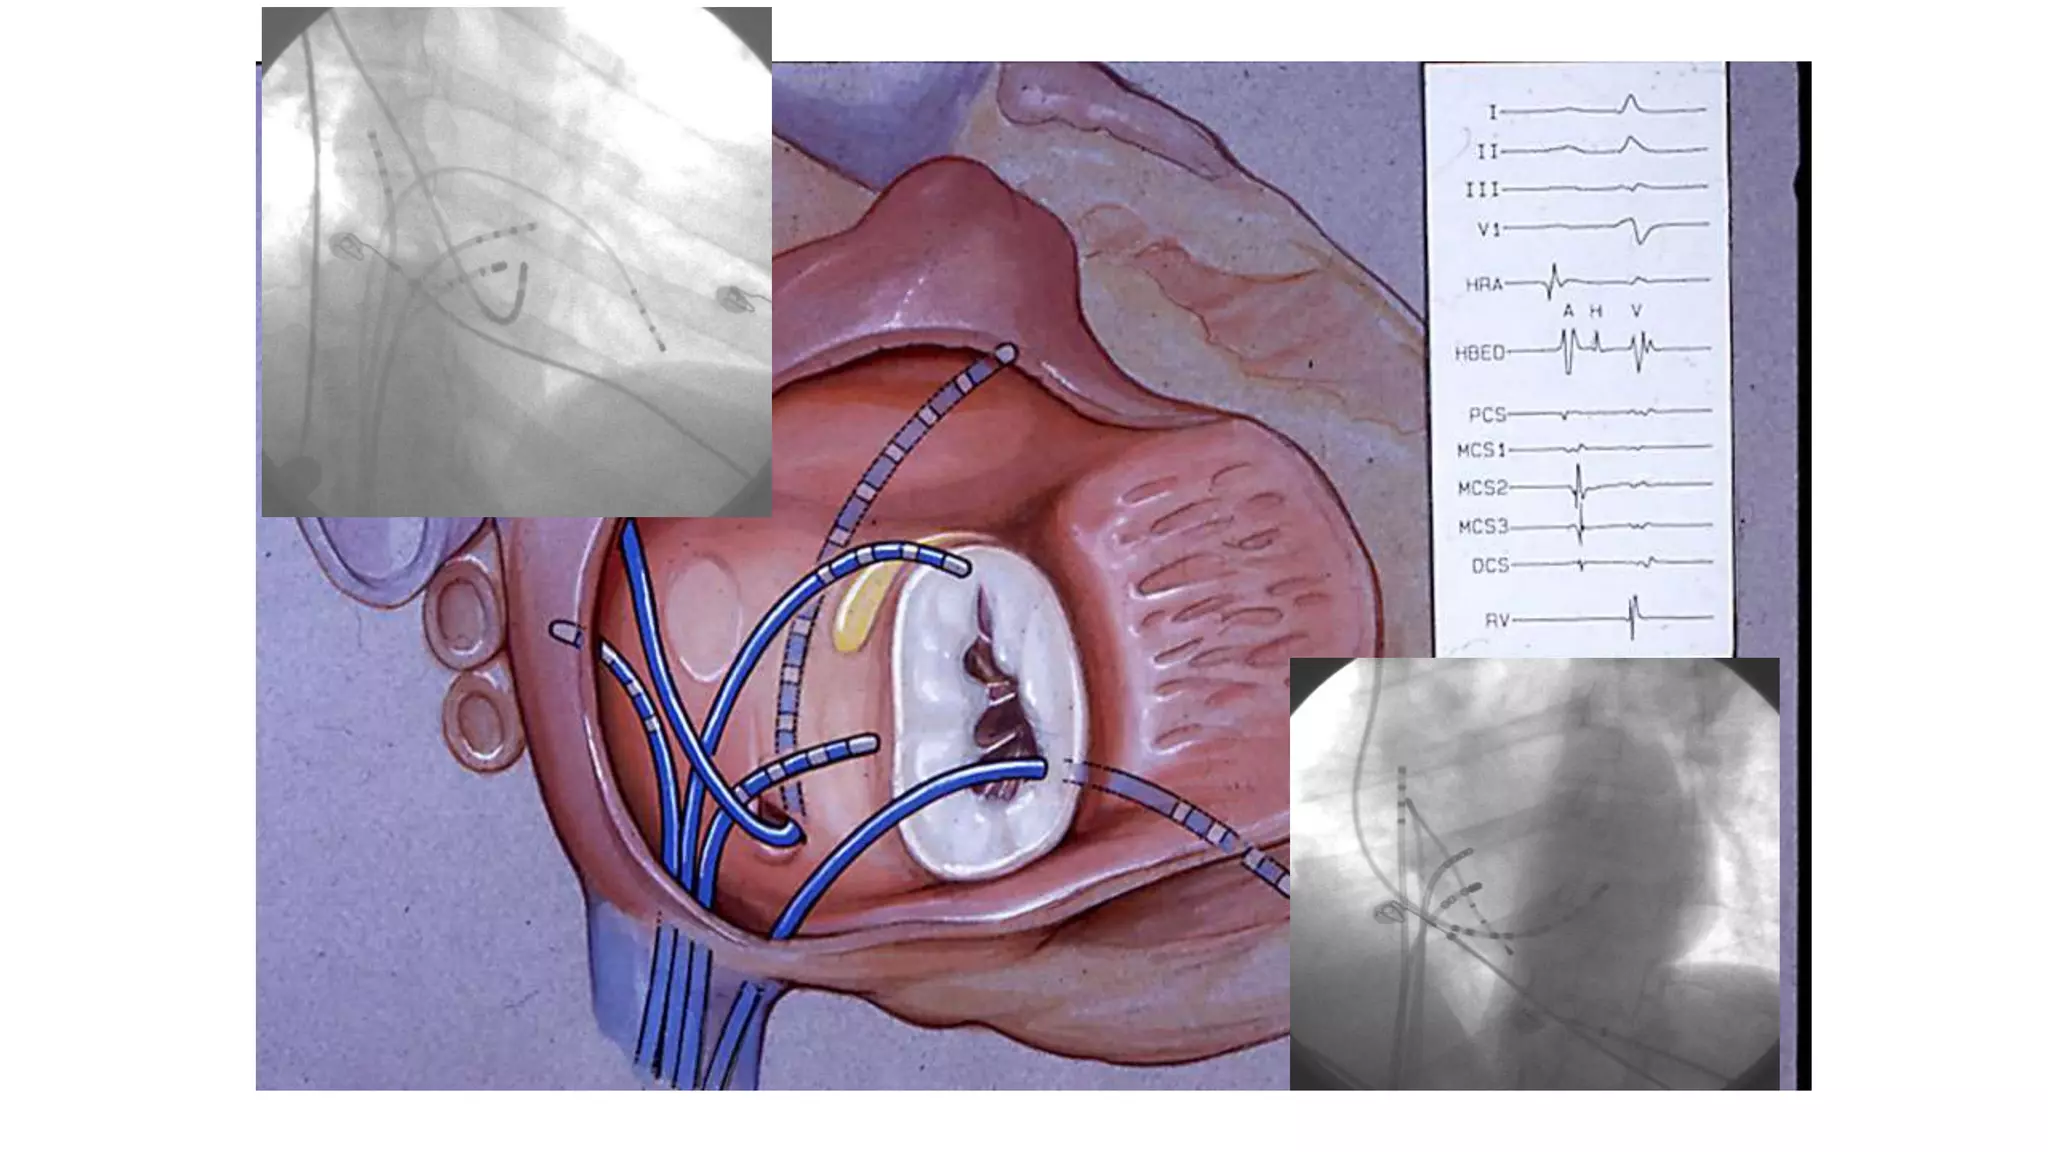

An electrophysiologic study involves inserting electrode catheters into the heart to record electrical activity and induce arrhythmias. The document discusses: 1. The procedure involves placing catheters in the heart to record electrograms from the atria, His bundle, ventricles and coronary sinus. 2. The aims are diagnostic to evaluate arrhythmias and bradycardias, and therapeutic for ablation of arrhythmias. 3. Key measurements taken include intervals between P waves, His bundle activation and QRS complex to identify conduction abnormalities. 4. Tracings are analyzed to determine the rhythm, sequence of activation, effects of pacing, and identify arrhythmia mechanisms like accessory pathways